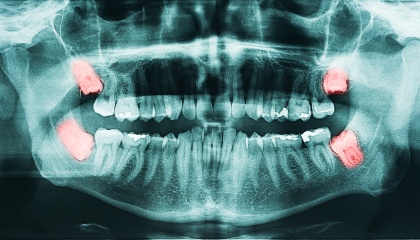

During your first visit, we'll delve into your medical history and have a comprehensive discussion about the wisdom teeth removal process. We'll take x-rays to assess the position and condition of your wisdom teeth, allowing us to create a customized treatment plan tailored to your specific needs. This plan will outline the costs, timeline, and steps involved in the procedure. We also encourage you to ask any questions you may have; we're committed to addressing any concerns you might have about the process.

- Impaction: Stuck in the jawbone and unable to erupt properly.